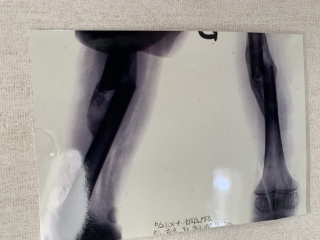

大腿骨骨幹部骨折

男子 10歳 スキーにて滑走中、誤って相手と接触、転倒して受傷した 小児の自家矯正力は旺盛なので、意識的に短縮位で固定をします。応変率で両下肢の長さが同じになります。